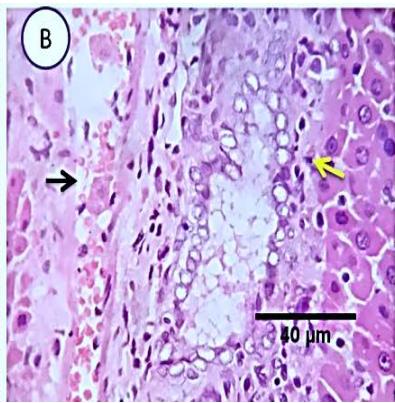

Liver: Examined sections from liver of this group denoted moderate portal biliary proliferation, congestion of portal blood vessels, round cell infiltration, multifocal interstitial lymphocytic and macrophages aggregations replacing previous necrotic patches beside degenerative changes in a few hepatocytes. (Fig.4).

Fig. 3: Photo-micrograph from liver, group (2), showing, portal biliary proliferation (yellow arrow), congestions of portal blood vessels (blue arrow) and round cell infiltration beside degenerative changes in a few hepatocytes. Scale bars 120, 20 um.